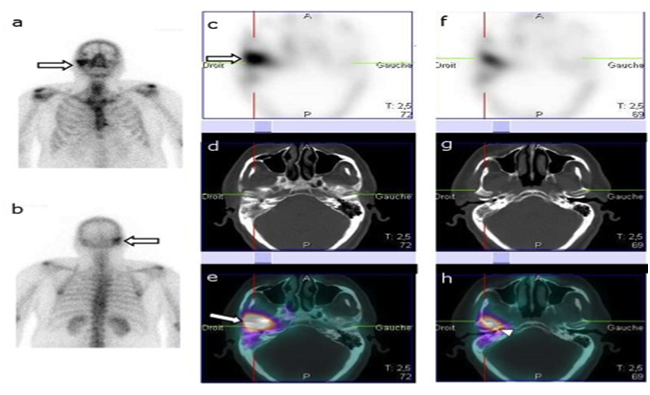

Figure 1, A 74year old non diabetic male, presented with severe otalgia and Otorrhea. The clinical exam showed inflammation and stenosis of the external auditory canal. Bone scintigraphy was performed for suspected NOE. Planar BS images (a, b) showed increased radiotracer uptake in the left temporal bone (arrow). SPECT images (c, f) showed also increased uptake in the left temporal bone. SPECT/CT Images (e, h) allowed accurate location of the site of involvement showing increased uptake in petrous portion (arrowhead) and mastoid process (arrow). CT images (d, g) showed osteolysis in the petrous portion of the temporal bone (arrowhead). On clinical follow up the patient started improving with systemic antibiotics and the final diagnosis was NOE.

Figure 1 The clinical exam showed inflammation and stenosis of the external auditory canal.